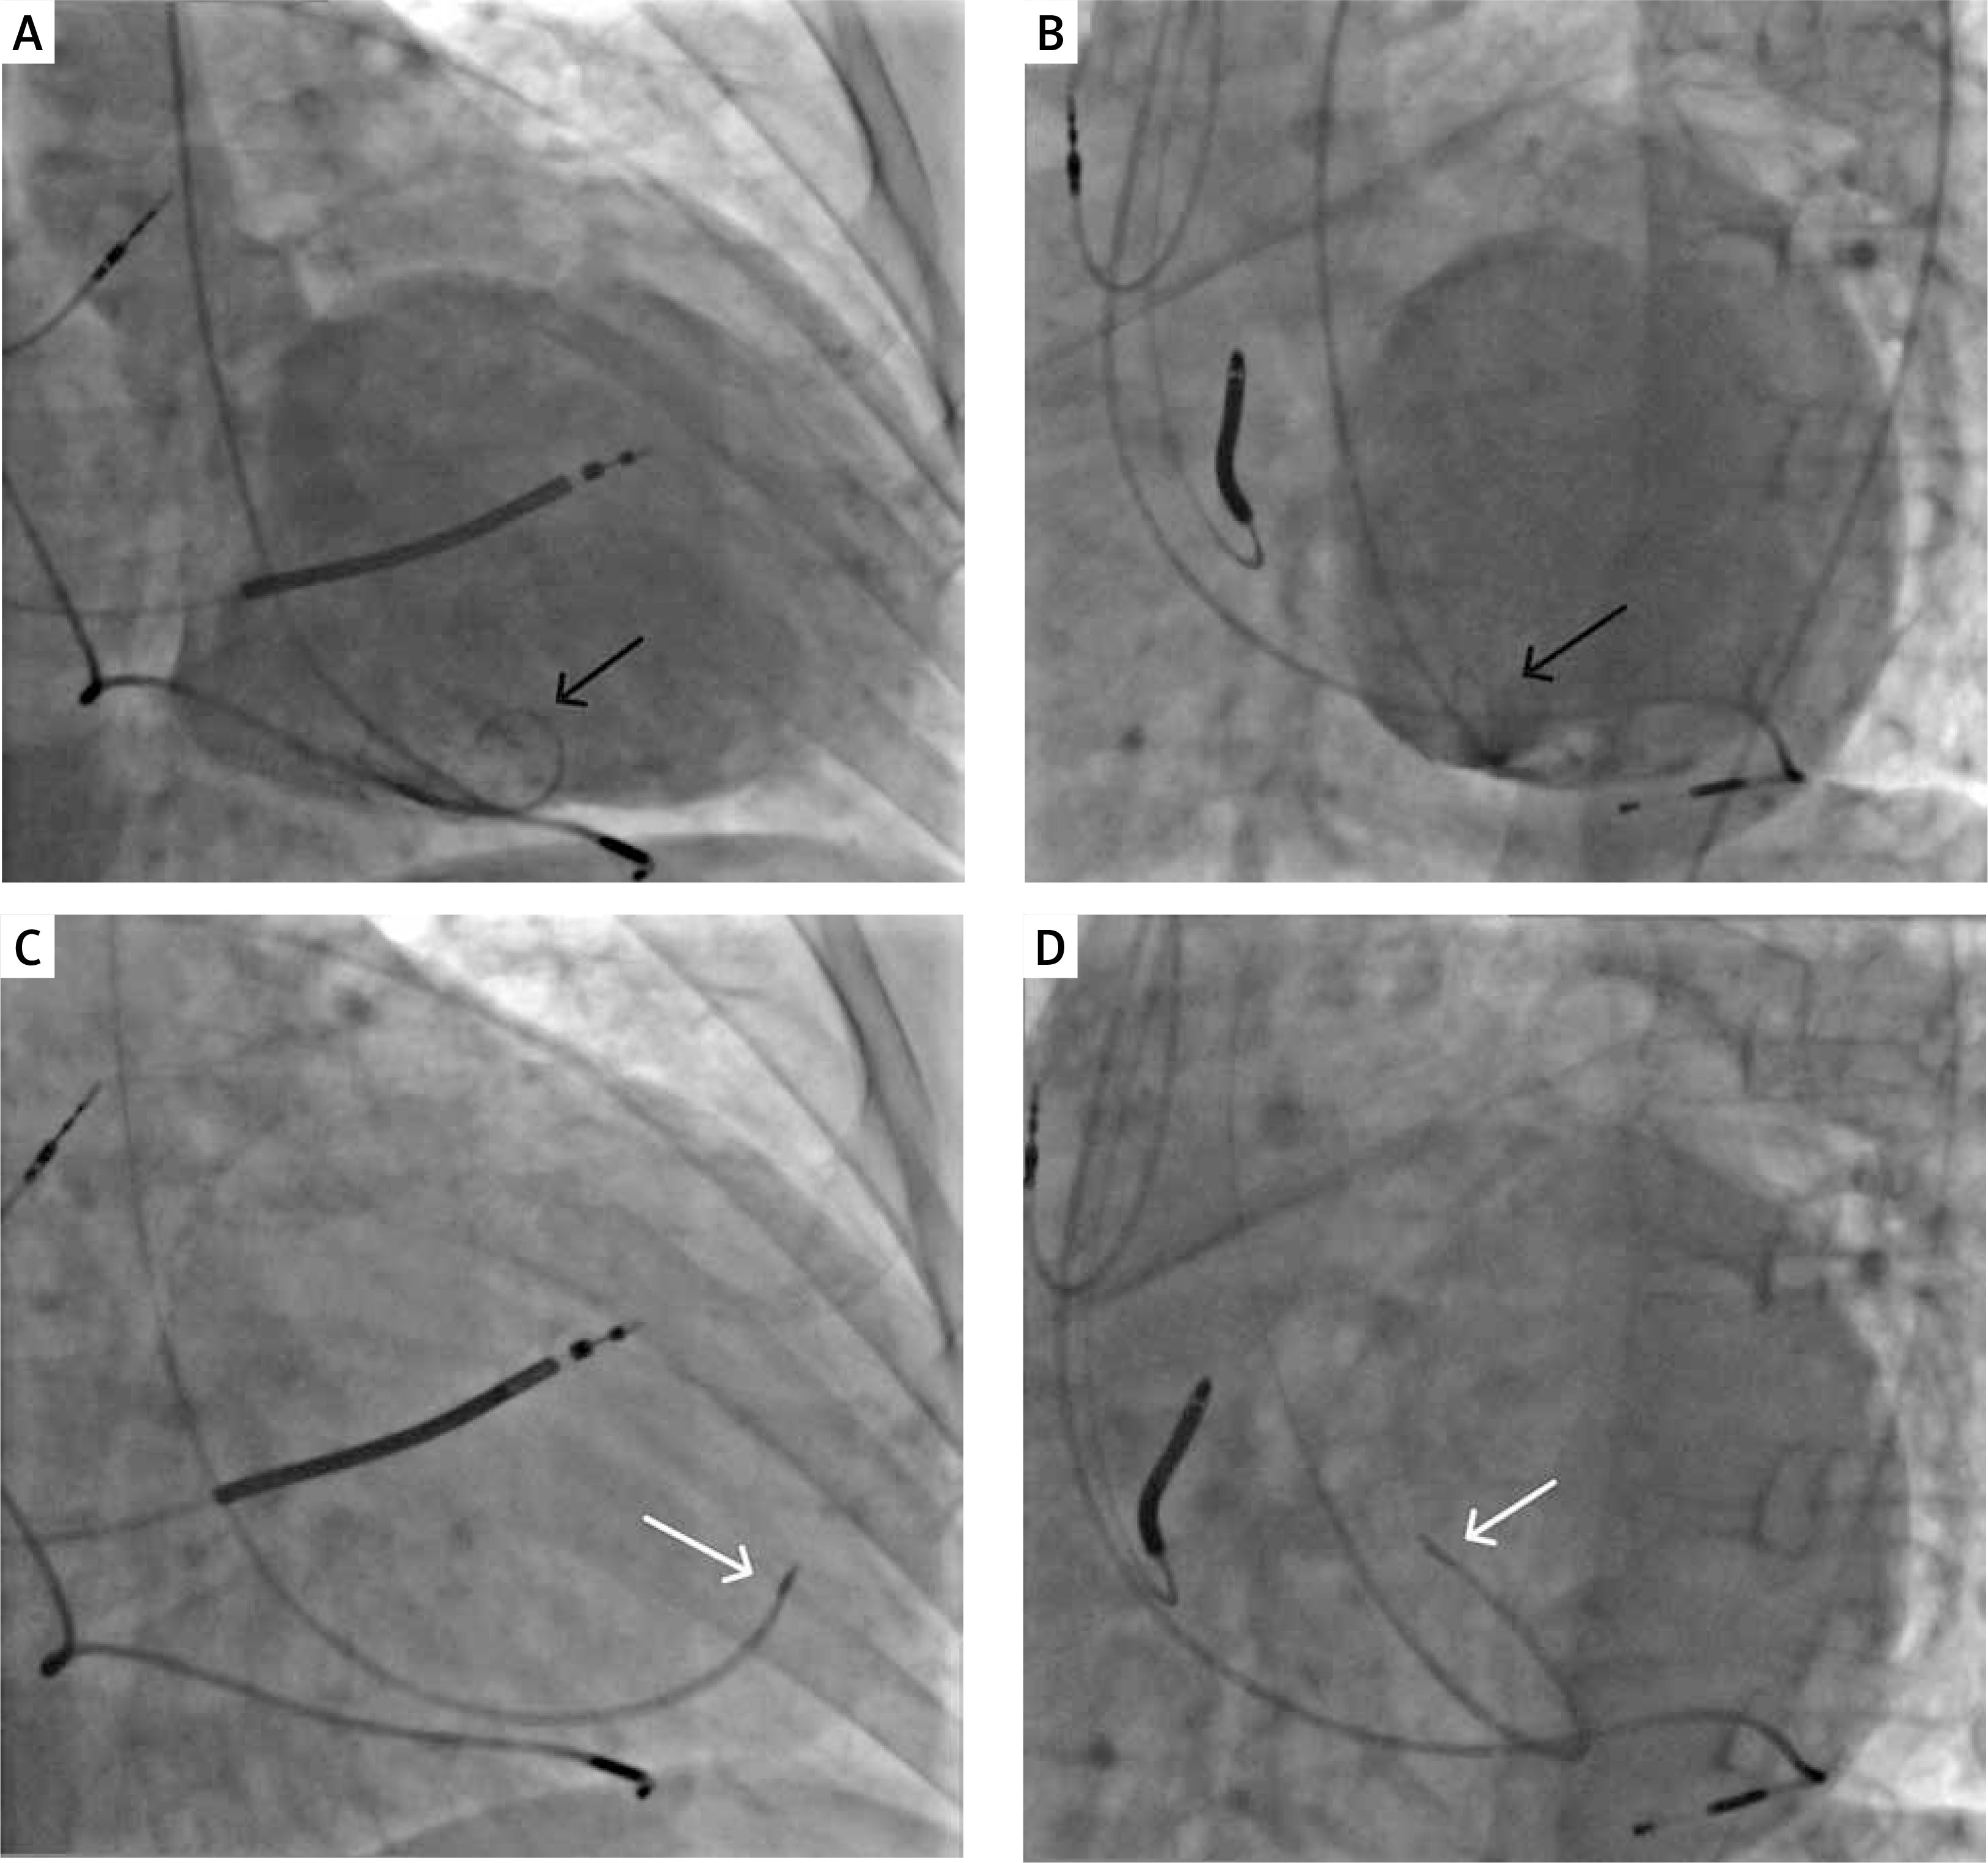

Mesenchymal stem cells were harvested from bone marrow and cultured in a central laboratory to achieve at least 24 million autologous CSCs from a harvest. Transendocardial injections (up to 20; 0.5 ml each) were administered into left ventricular wall segments with impaired contractility and a wall thickness ≥ 8 mm, avoiding the area of the mitral and aortic valves. Target zones were chosen and confirmed with left ventricular angiography and periprocedural echocardiography. The procedure was done with C-Cath, curved, multi-perforated needle (side holes) catheter, designed to enhance cell delivery [15, 16]. For a sham procedure, a pigtail catheter was placed in the left ventricular cavity, and saline injections were performed ‘targeting’ specific zones as in active procedures (Figures 1, 2). Patients were followed for 30 days after the procedure for procedure-related adverse events.

Figure 1

An example of an intracardiac, trans-catheter, needle-based, cardiopoetic stem-cell delivery procedure. A, B – Ventriculography (A – antero-posterior (AP) and B – left anterior oblique (LAO) view) prior to trans-endocardial cell delivery; black arrows indicate the tip of pigtail catheter; C, D – injection catheter attached to the target cardiac wall in the corresponding projection (C – AP, D – LAO view); white arrows indicate the tip of a needle-tipped catheter for cell delivery